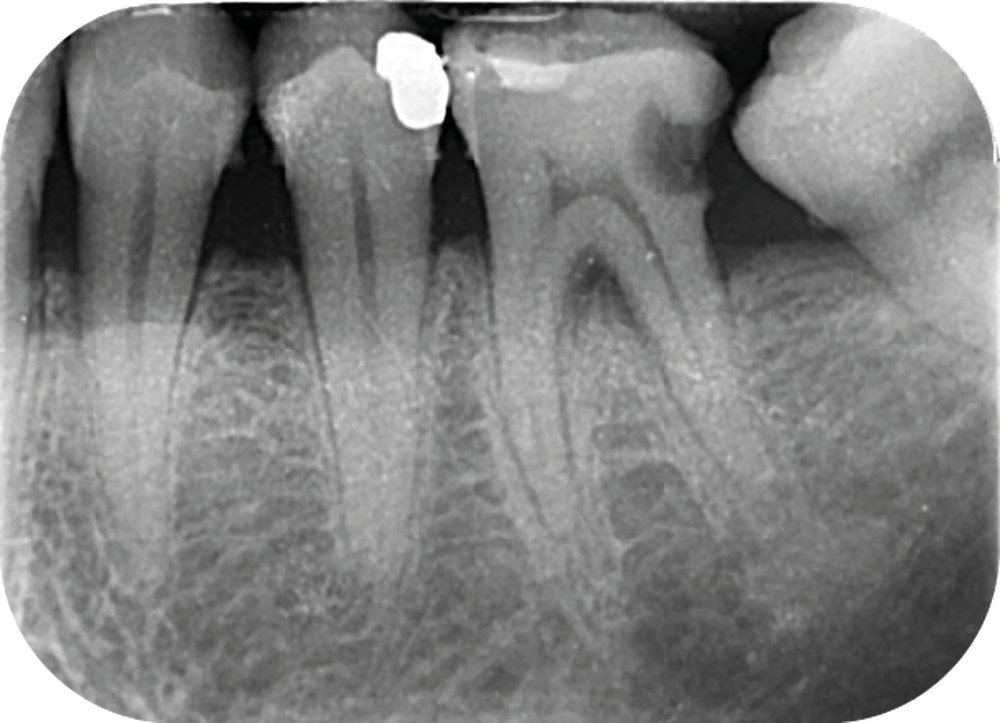

Cette version, quand elle se produit, modifie les espaces interdentaires et complique l’hygiène proximale des patients. Des caries peuvent alors se développer en interproximal sans que cela soit forcément visible à l’examen visuel (fig. 3 et 4). Les radios de type bite-wing (rétro-coronaires) prennent alors tout leur sens (fig. 5 et 6).

La version des dents distales peut aussi avoir des conséquences parodontales désastreuses : sur un parodonte réduit, une hypermobilité peut se développer, une poche parodontale peut aussi apparaître. Chez un patient parodontal, un « effet domino » est possible, des extractions non compensées diminueront donc le pronostic des dents restantes (fig. 7 à 9).

La répartition de la charge occlusale sur l’ensemble d’une arcade est aussi perturbée après une ou plusieurs extractions, ce qui peut occasionner des surcharges occlusales pour les dents restantes. Selon le délabrement coronaire de la dent [10], une fracture coronaire amélo-dentinaire ou corono-radiculaire peut intervenir sous cette surcharge occlusale et engager le pronostic de la dent concernée (fig. 14 à 17).